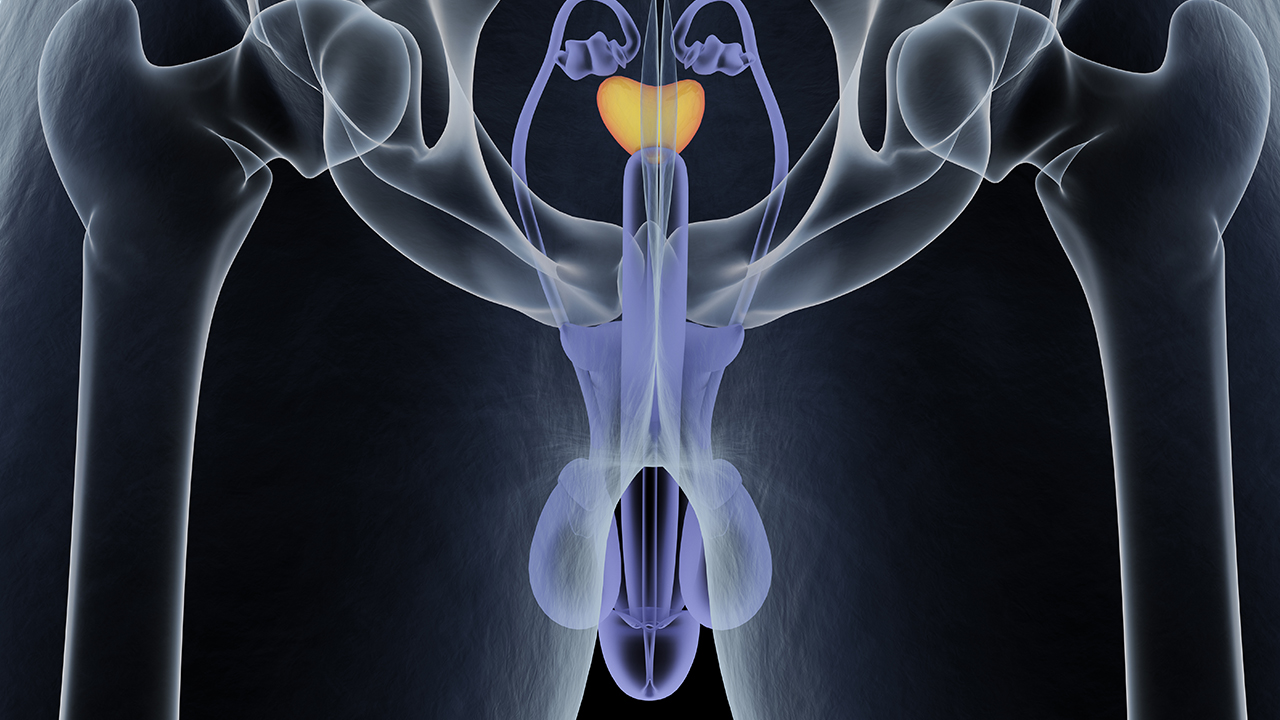

包皮手术是什么科

包皮手术通常属于泌尿外科,泌尿外科诊治泌尿系统及男性生殖系统疾病,包皮是男性生殖系统一部分,包皮过长、包茎等需手术时由泌尿外科医生操作,儿童包皮相关问题手术也多由其处理,成年男性因包皮过长致反复龟头炎等也需到泌尿外科就诊考虑手术,不同医院科室设置有细微差异,基层医院无单独泌尿外科时可能归外科但总体包皮手术与泌尿外科相关。